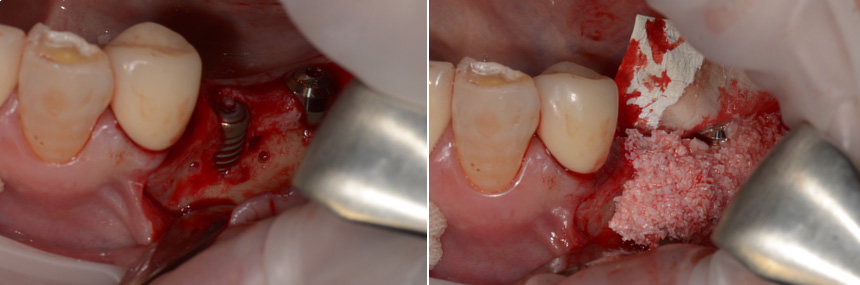

骨の形によっては、インプラントを埋入すると一部が口の中に露出することがあります。露出した部分をそのままにすると細菌が集まり、骨が吸収する原因となるので、露出した部分には人工骨などで覆い骨を作ります。先に人工骨で骨を作り、しっかりと骨ができた段階でインプラントを埋入することもあります。

インプラントを埋入すると部分的に露出したので人工骨で覆いました。